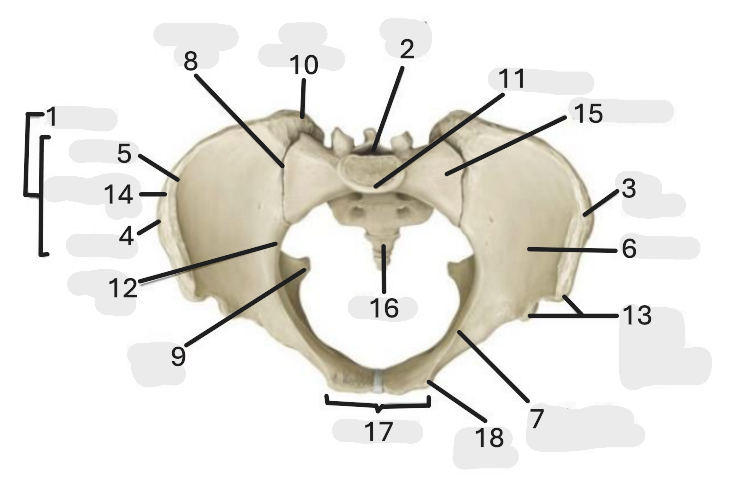

Where is the pelvic inlet

1

Where is the sacro-iliac joint

2

Where is the pubic tubercle

3

Where are the S1 body

4

Where is the ischial spine

5

Where is the ala of sacrum

6

Where is the anterior superior iliac spine

7

Where is the ischiopubic ramus

8

Where is the coccyx

9

Where is the obturator foramen

10

Where is the pubic symphysis

11

Where is the ischial tuberosity

12